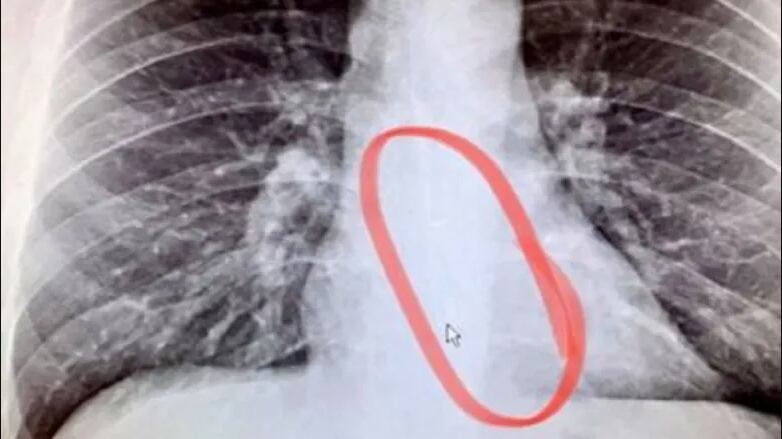

Bellmer, de 27 años, aseguró en su TikTok que gracias a una radiografía confirmó que tenía el AirPod de Apple en su estómago y que afortunadamente luego pudo expulsar de manera natural y sin intervención médica.